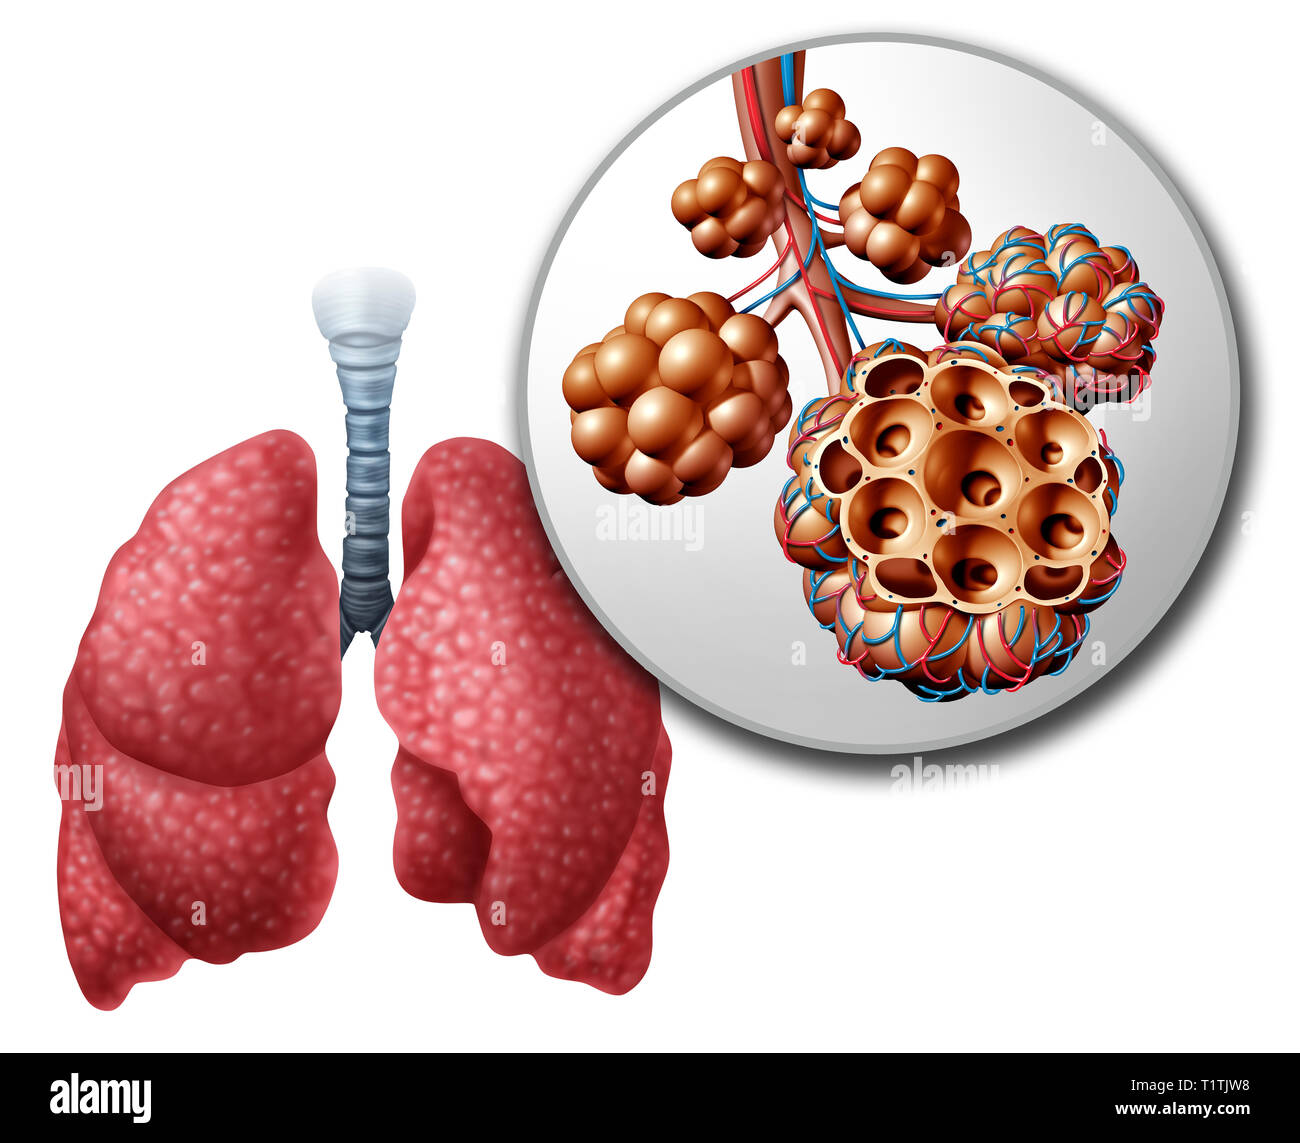

CrossFit | Lung Anatomy: The Airway And Alveoli

www.crossfit.com

www.crossfit.com

alveoli lung bronchioles clusters adjacent crossfit airway alveolus capillaries packed densely terminus buttress